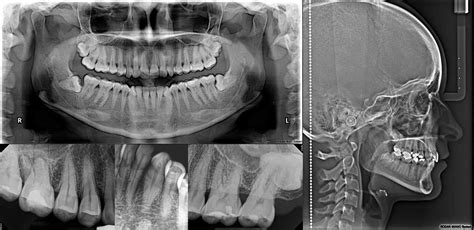

Las radiografías dentales se clasifican en dos grandes grupos: intraorales y extraorales. Las radiografías intraorales son aquellas en las que la película o el sensor se coloca dentro de la boca. Son las más comunes y detalladas, proporcionando una visión precisa de los dientes y las estructuras adyacentes.

Radiografías Extraorales

Las radiografías extraorales son técnicas de diagnóstico por imagen en odontología en las que el sensor o película radiográfica se coloca fuera de la boca del paciente. Es fundamental para los análisis cefalométricos que determinan la posición y alineación de los dientes, así como la relación entre los maxilares y el cráneo.